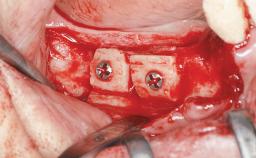

A 45-year-old woman with a completely edentulous maxilla was referred to evaluate the possibility of rehabilitation with an implant-supported prosthesis. This patient was healthy and a non-smoker. She had been wearing a maxillary complete denture opposing a natural mandibular dentition since her twenties. This situation had resulted in progressive resorption of the alveolar ridge, repeatedly creating a need for relining the denture. Twenty years later, despite multiple adaptations and the use of “glues” the denture was unstable and causing the patient psychological and functional discomfort.

Bone Augmentation Horizontal|Sinus Floor Elevation|Staged|Vertical

Augmentation Materials Autogenous chips|Autogenous block(s)

Bone Volume Deficient vertically or deficient vertically AND horizontally